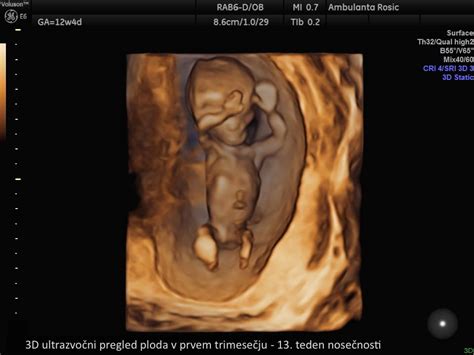

Prvo trimesečje (1. do 12. teden)

Prvi trije meseci so ključni za postavitev temeljev otrokovega razvoja. Kljub temu, da so znaki nosečnosti sprva subtilni, se v tem obdobju zgodi izjemen napredek.

- 11.-12. teden: Glava zavzema polovico velikosti ploda. Razvijejo se očesne veke in zametki zob. Formirajo se jetra, zunanje genitalije, nastanejo nohti. Plod meri 4-5 cm. Nastanek organov je skoraj zaključen, posteljica že oskrbuje plod s hrano in kisikom.

- 13.-14. teden: Na prstih se razvijajo prstni odtisi. Zasnovani so vsi mlečni zobje. Trebušna slinavka prične izločati inzulin. Na ultrazvoku je mogoče določiti spol. Plod meri približno 7 cm in tehta 20 gramov. Opazni so dihalni gibi, plod požira plodovnico in izloča urin.